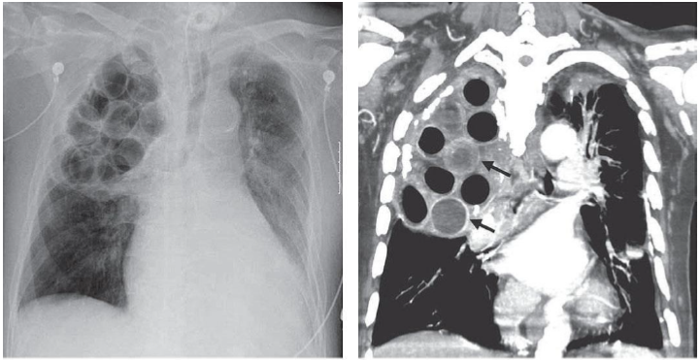

Um paciente de 70 anos foi admitido em uma Unidade de Pronto Atendimento (UPA), vítima de queda da própria altura com trauma torácico direito. Apresentava-se lúcido, eupneico e hemodinamicamente estável. Relatou história de internação e cirurgia aos 20 anos, por tuberculose pulmonar. Foi solicitada uma avaliação por imagem, obtendo-se as representações a seguir:

Após avaliar as imagens, a equipe médica constatou que o paciente foi submetido, à época, ao procedimento cirúrgico de: